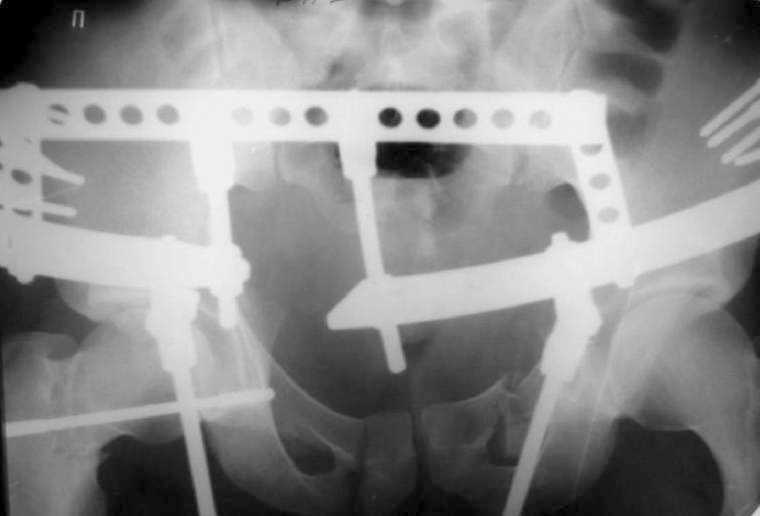

A 23 y.o. male after a car accident transferred to us from elsewhere at 4th day since the injury. He has the pelvic ring lesion including fracture of the left acetabulum, and ipsilateral femoral neck and shaft fractures - images attached. The shaft fracture is open grade II, debrided at the initial hospital - no sign of infection to date.

I found inlet and one Judet view. CT is not available - the CT machine is in another building. In the next message i attached three views in external fixator.

See attachment for AP and Judet views after external fixation. Our pelvic guys tried to reduce the acetabulum with the transarticular pin inserted through the lower part of the head. They are satisfied with the pattern and plan to insert a percutaneous screw to fix the position during a surgery for the neck and shaft fracures.